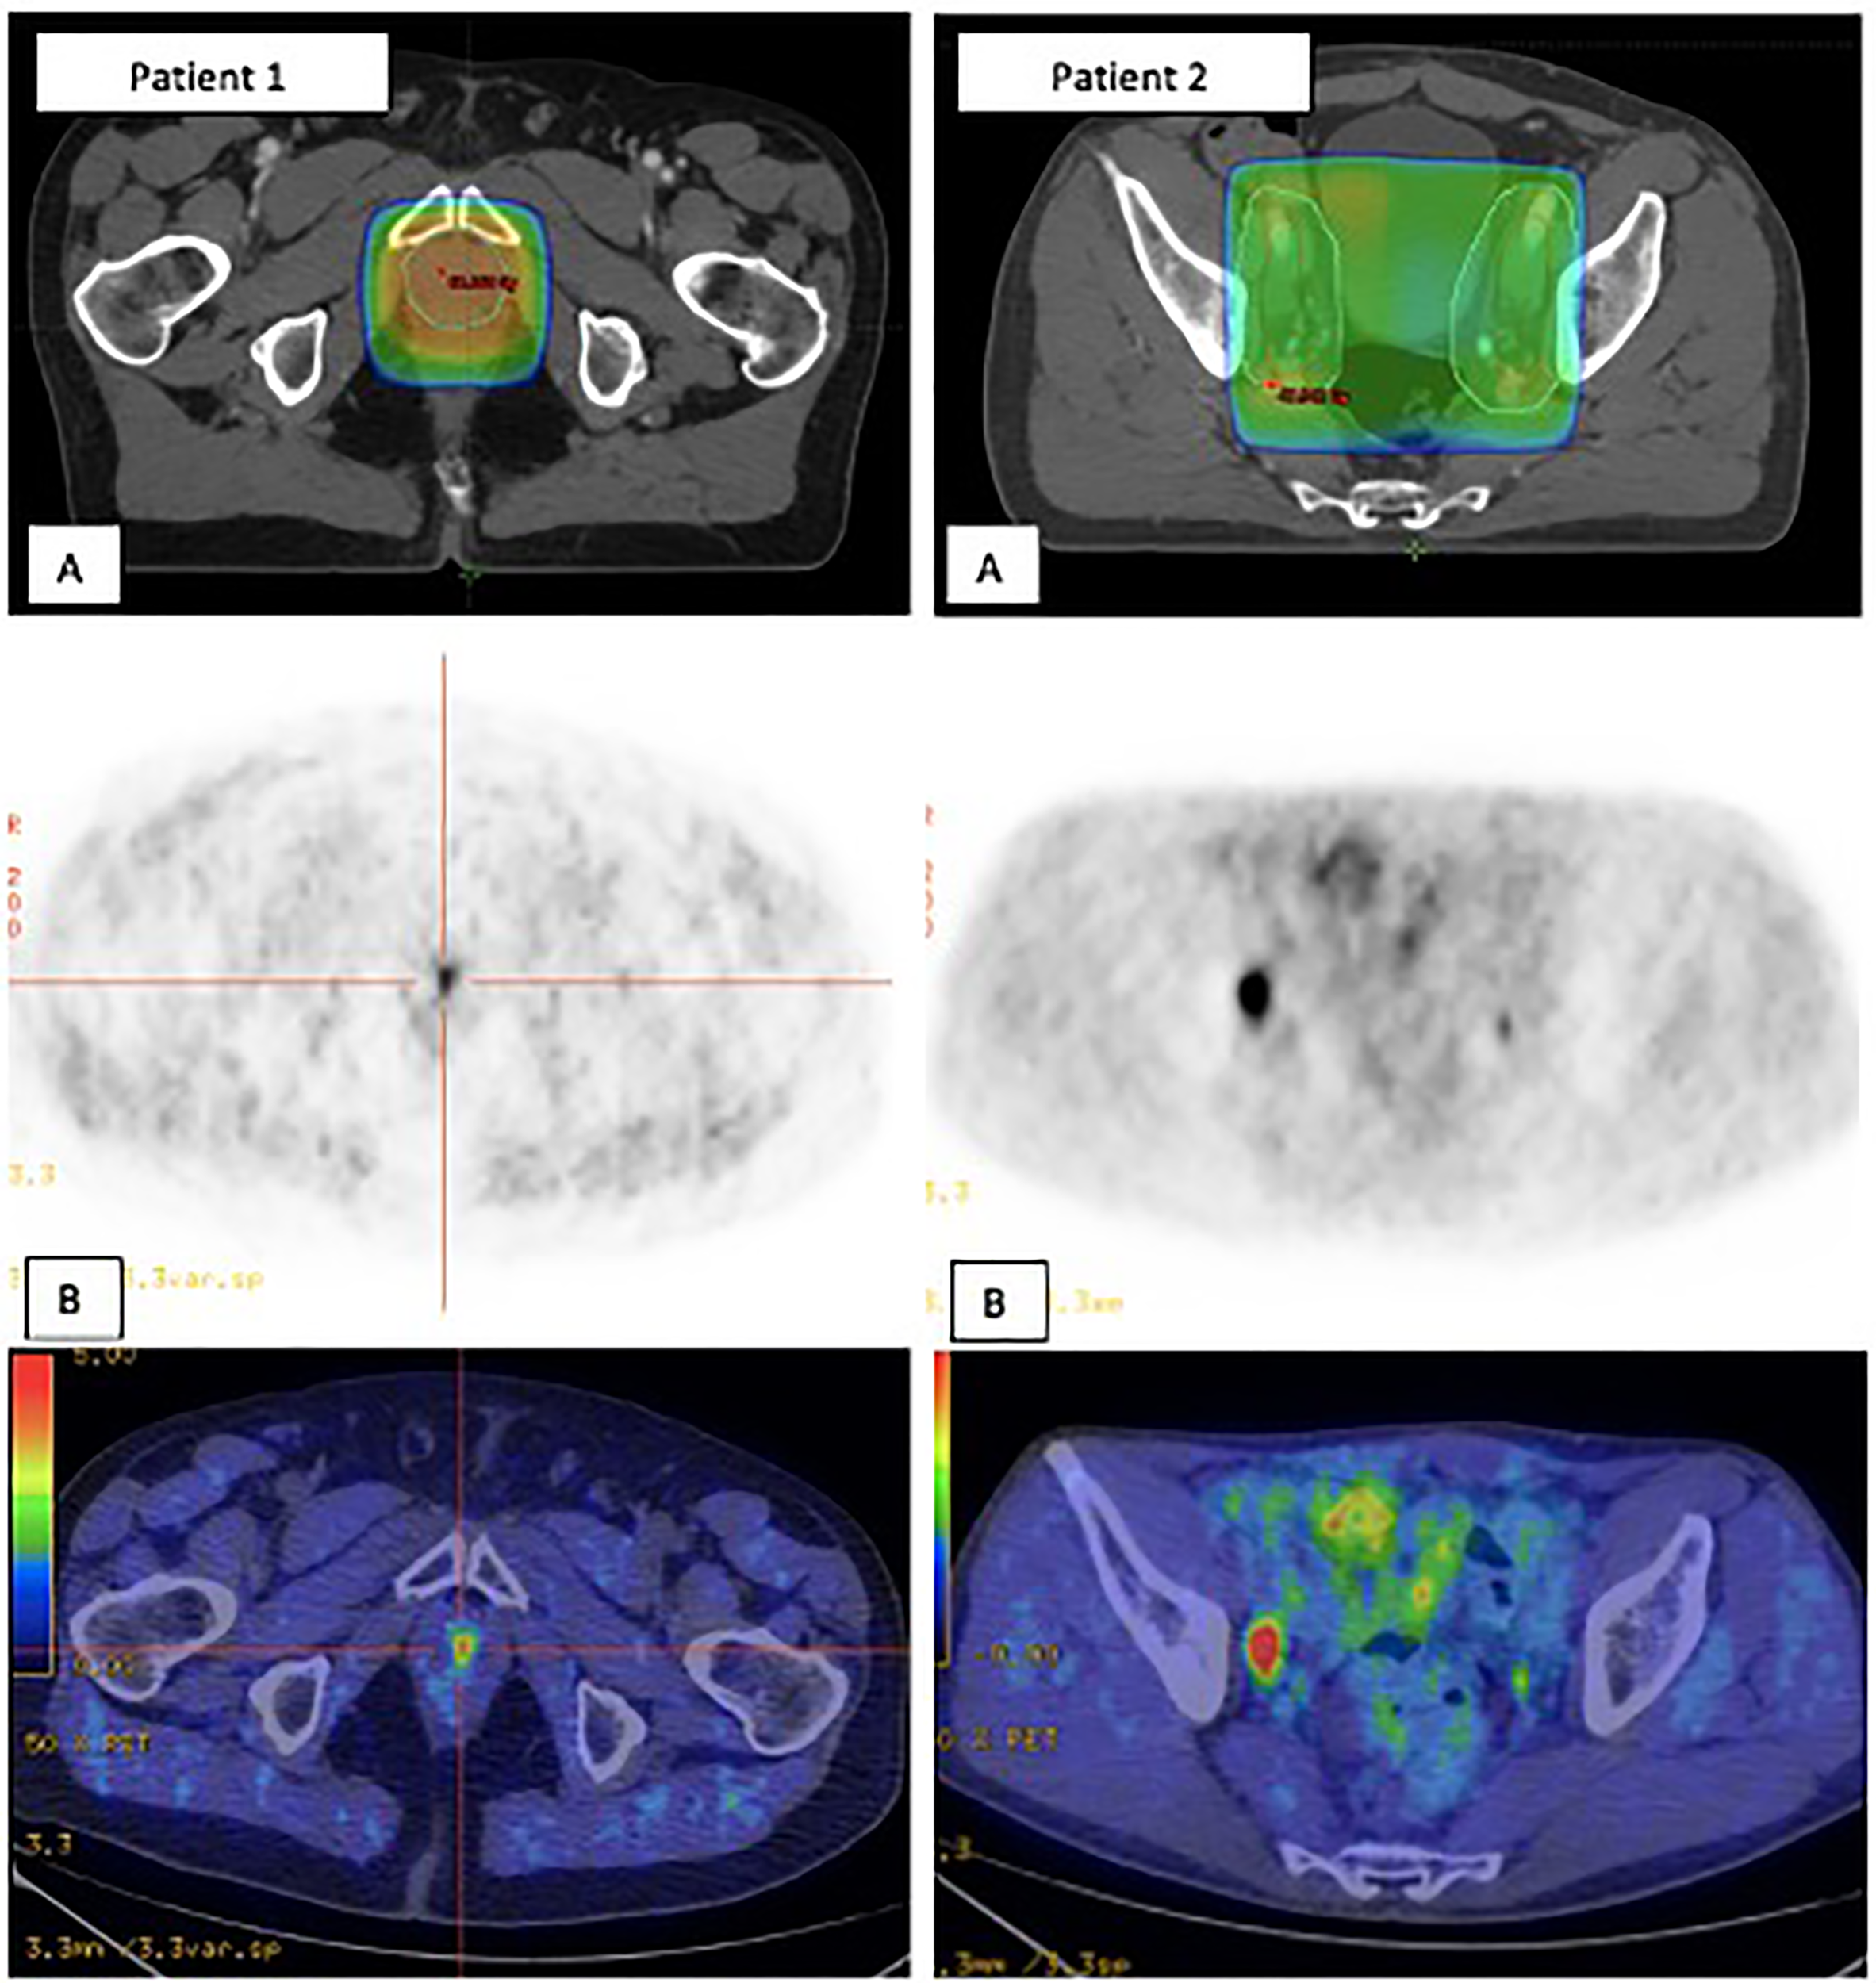

Sites of recurrence and their relationship to prior RT planning fields, both for the PB alone and the PB+PLN groups, are summarized in Table 3. Of the 108 patients treated to the PB alone, isolated infield failure occurred in 4 patients (4%) and all recurred within the radiation isodose 66 Gy (patient’s example 1 in Figure 4). In these group, 104 (96%) failed out of the previous radiation field; half of them (n = 56, 52%) had locoregional disease and 48 (44%) had metastatic disease. Notably, 53 of the 122 pelvic nodal recurrences (48%) might have been encompassed by the addition of the standard PLN volume (PTV to L5-S1 fields). In the PB+PLN group, two of 33 patients (6%) had local-only failure. Five of 33 patients (15%) had pelvic nodal failure alone: four were located within the PLN RT field, and one located just outside the RT volumes in the pararectal area. In these group, 26/33 patients (79%) had metastatic disease: none of the 33 patients (27%) had distant LN, 12/33 (40%) had either bony or visceral metastases, and five of 33 (15%) had multisite failure. Five patients had nodal failure both within the pelvis and distant LN: four patients had LN within RT fields and one had presacral LN located just above the RT volume.

Figure 4

Two patients’ examples of in-field recurrences (A) which were positive on Choline PET/CT (B). Patient 1. Urethral anastomosis failure within the PB RT volume. Patient 2. Right iliac extern nodal failure within PLN RT volume. PB, Prostate bed; PET-CT, Positron emission tomography-computed tomography; PLN, Pelvic lymph nodes; RT, Radiotherapy.